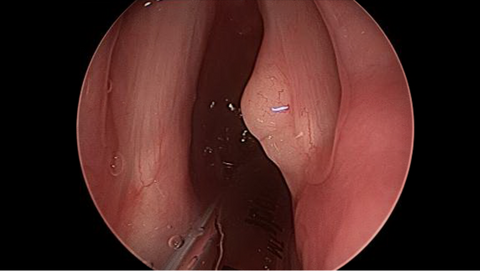

Fiberoptic Transnasal Laryngoscopy Showed a smooth yellow lesion on the dorsal surface of the right vocal process; laryngoscopy also showed abundant of lymphoid tissue in the adenoid fossa.

Preoperative Images